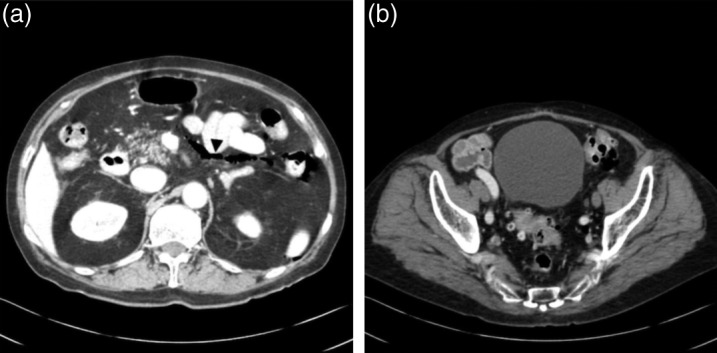

未标记:胃肠道穿孔是与类固醇治疗或高皮质醇血症相关的并发症,但在临床实践中很少在库欣病患者中观察到,只有一例被报道为首发症状。在此,我们报告一个罕见的病例库欣病,其中一个病人提出胃肠道穿孔作为症状。男,79岁,自诉下腹不适6个月。根据内分泌和胃肠检查,他被诊断为库欣病,伴有降结肠穿孔。在与胃肠外科医生会诊后,由于轻度全身性炎症和缺乏腹部保护,决定结肠穿孔可以保守观察,不需要任何口服摄入,并通过肠外给药抗生素治疗。尽管血清皮质醇水平明显升高,但由于结肠穿孔,口服药物不是一种选择。因此,患者接受鼻内腺瘤切除术以使血清皮质醇水平正常化。随后,成功进行了结肠造口术。尽管罕见,但医生应该意识到胃肠道穿孔可能与高皮质醇血症有关,特别是在老年患者中,立即诊断和治疗这种危及生命的疾病是至关重要的。如果穿孔可以保守地观察到,在剖腹手术前进行鼻内腺瘤切除术是高皮质醇症的另一种治疗选择。学习要点:迄今为止,仅报道了一例胃肠道穿孔作为库欣病的临床表现。医生应该意识到胃肠道穿孔可能与老年患者高皮质醇血症有关,因为血清皮质醇水平升高可能掩盖穿孔的临床症状。由于这种掩蔽效应,穿孔的诊断也往往延迟。虽然肠外给药依托咪酯是降低血清皮质醇升高水平的标准治疗选择,但如果没有依托咪酯治疗,剖腹手术前鼻内腺瘤切除术是另一种治疗选择。

Unlabelled: Gastrointestinal perforation is a complication associated with steroid therapy or hypercortisolism, but it is rarely observed in patients with Cushing's disease in clinical practice, and only one case has been reported as a presenting symptom. Herein, we report a rare case of Cushing's disease in which a patient presented with gastrointestinal perforation as a symptom. A 79-year-old man complained of discomfort in the lower abdomen for 6 months. Based on the endocrinological and gastroenterological examinations, he was diagnosed with Cushing's disease with a perforation of the descending colon. After consultation with a gastroenterological surgeon, it was decided that colonic perforation could be conservatively observed without any oral intake and treated with parenteral administration of antibiotics because of the mild systemic inflammation and lack of abdominal guarding. Despite the marked elevated levels of serum cortisol, oral medication was not an option because of colonic perforation. Therefore, the patient was submitted to endonasal adenomectomy to normalize the levels of serum cortisol. Subsequently, a colostomy was successfully performed. Despite its rarity, physicians should be aware that gastrointestinal perforation may be associated with hypercortisolism, especially in elderly patients, and immediate diagnosis and treatment of this life-threatening condition are essential. If a perforation can be conservatively observed, endonasal adenomectomy prior to laparotomy is an alternative treatment option for hypercortisolism.